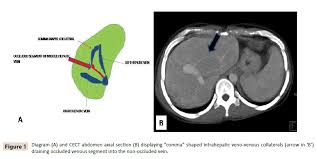

Chiasmata -mə-tə or chiasmas also chiasms 1. Esophageal varices are extremely dilated sub-mucosal veins in the lower third of the esophagus. Located in metro Denver northern Colorado and western Nebraska serving all of the Front Range our team consists of board-certified and fellowship-trained interventional radiologists. This results in hepatic congestion similar to Budd-Chiari syndrome and post-sinusoidal portal hypertension. The patients condition should be monitored throughout the procedure. They are most often a consequence of portal hypertension commonly due to cirrhosis. Toxic injury to liver sinusoids causes sloughing of endothelial cells that embolize to hepatic venules and cause eventual fibrosis of the venules. Coin in the Esophagus. There is no clear consensus regarding the number of occluded veins some authors claim that there should be at least one occluded hepatic vein 7 others state that there are no significant.

Carcinoma of the Colon. Budd-Chiari syndrome a blockage in one or more veins that carry blood from the liver back to the heart. And coumarin skin necrosis adrenal gland hemorrhage and infarction. Toxic injury to liver sinusoids causes sloughing of endothelial cells that embolize to hepatic venules and cause eventual fibrosis of the venules. Chiari malformation CM is a structural defect in the cerebellum characterized by a downward displacement of one or both cerebellar tonsils through the foramen magnum the opening at the base of the skull. Embolism and thrombosis of. La présence dune ou plusieurs affections prothrombotiques est fréquente La prise en charge repose sur un traitement anticoagulant précoce le traitement de l.